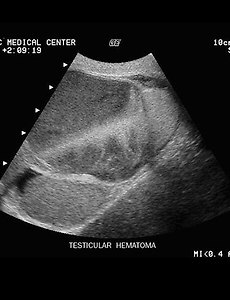

Torsion Torsion. The testicle is attached to the scrotum at the bare area. If the bare area is small, a tiny remnant stalk of tunica vaginalis allows the testicle to be mobile. Torsion occurs when the testicle revolves one or more times on this short stalk, which obstructs blood flow to the testicle, resulting in severe pain. Torsion is more common in males under 25 years of age with a peak incidence at.. 2009. 9. 21. 이전 1 다음